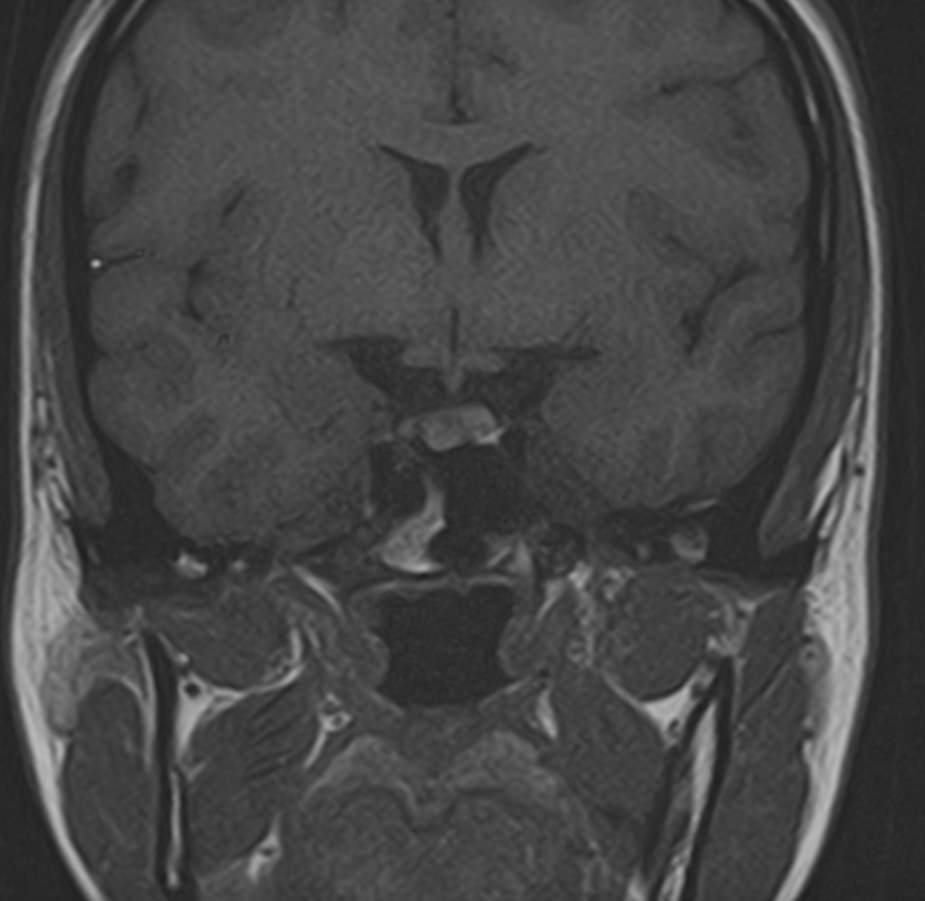

Поскольку гипофиз имеет очень маленькие размеры и расположен в глубине головы, досконально изучить его структуру можно только с помощью МРТ. Ни один другой из существующих методов визуализации не способен дать настолько четкие изображения и данные о состоянии гипофиза. Расшифровка результатов выполняется рентгенологом.

С помощью МРТ гипофиза можно создать его трехмерное изображение с высокой степенью детализации. Это позволяет обнаружить патологические изменения на самых ранних этапах, начиная от аномалий развития, сосудистых нарушений, воспалительных процессов и заканчивая опухолями разной природы.

МРТ гипофиза выполняется в нашей клинике выполняеется только с контрастным усилением, что повышает четкость получаемых изображений, а по особенностям распределения контрастного препарата в тканях можно с высокой точностью не только обнаружить доброкачественные и злокачественные опухоли, но и исследовать их локализацию, структуру, определить границы и заметить метастазы.

Чаще всего исследование проводится для диагностирования аденомы гипофиза и определения ее величины: микроаденомы (до 10 мм), макроаденомы (10—30 мм) и гигантской аденомы (более 30 мм). Также с его помощью обнаруживается неоднородностьструктуры, асимметрия границ, изменения положения воронки гипофиза и ее строения, а также деформации окружающих костных тканей.